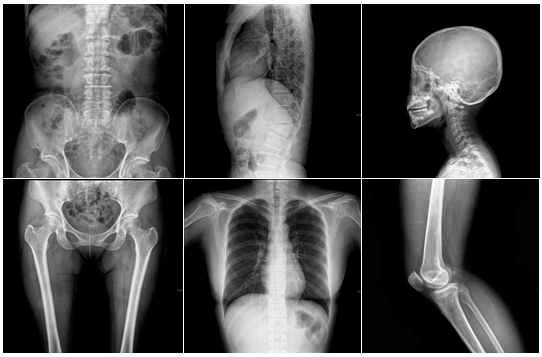

Los objetos más extraños que las personas se metieron al cuerpo en 2017

Siguiendo con las recopilaciones del 2017, esta vez presentamos un conteo peculiar: Los objetos más extraños que las personas se metieron al cuerpo en 2017.

Siguiendo con las recopilaciones de lo mejor y peor del año, esta vez presentamos un conteo peculiar: Los objetos más extraños que las personas se metieron al cuerpo en 2017.

Objetos más extraños en el cuerpo de las personas

Desde oído, nariz, garganta, pene, vagina y recto; la lista de objetos más extraños que las personas se metieron al cuerpo este 2017 es bastante larga. Cabe aclarar que este conteo abarca únicamente a las personas nacidas en Estados Unidos, y se basa en historiales de urgencias emitidos por la Comisión para la Seguridad de los Productos de Consumo en aquel país. Por gusto, accidente o simplemente por locura, las personas asistieron a las salas de urgencia para que les extrajeran estos objetos alojados en diferentes partes de su cuerpo.Peculiares ejemplos